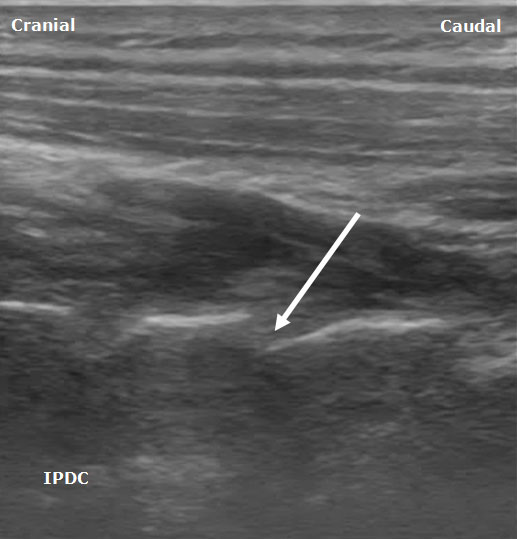

A high frequency linear array transducer is needed for visualization of the cervical medial branches and facet joints. Multiple ultrasound techniques have been described to visualize the cervical facets and associated medial branches.[5-9] The first technique involves positioning the patient in the lateral decubitus position.[7] Initially the transducer is placed over the mastoid process in the longitudinal axis. The transducer position is optimized to view the transverse processes of C1 and C2. The vertebral artery between C1 and C2 can often be visualized. Next, the transducer is moved posteriorly and caudad in the longitudinal plane. The third occipital nerve is identified. The third occipital nerve exists 1 mm from the bony elements. Once the third occipital nerve has been identified and the associated C2-C3 facet, these landmarks can be used for counting as the transducer is moved caudad over the remaining cervical facet joints (Figure 2). The remaining cervical medial branches are identified around each respective neck of the articular pillar (i.e. depressed area). The nerves typically are hypoechoic structures with internal hyperechoic areas (Figure 3).

Figure 3. A longitudinal ultrasound image of the cervical spine demonstrating the cervical medial branches (arrows) and associated cervical facet joint (circle).

Ultrasound Technique For Cervical Medial Branch and Facet Intra-Articular Injection

After the cervical medial branches are identified by the above description, a needle is inserted out of plane (short axis).7 The needle is advanced until it is adjacent to the medial branch. After insuring the lack of vascular structures in the region of the needle with ultrasound imaging and negative aspiration, 0.3-0.5 mL of local anesthetic is injected. It is preferable to advance the needle from anterior to posterior since the neural foramen and vertebral artery are anterior to the cervical facets. Eichenberger et al.6 described in detail the sonographic visualization and the ultrasound-guided block specifically for the third occipital nerve. Needles were positioned correctly in 82% of cases.